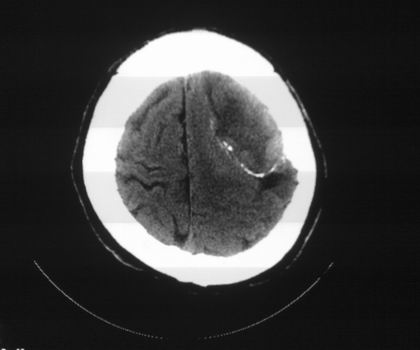

以下是引用影像孺子牛在2008-4-29 21:20:00的发言:[br]首先病变定位在脑外,根据ct密度及mri信号特征考虑慢性硬膜下血肿不连续环形钙化。

以下是引用周战梅在2008-4-29 23:12:00的发言:[br]脑外病变,蛛网膜下腔增宽,囊壁点状、环形钙化,增强扫描呈不均匀环状强化,考虑为囊性脑膜瘤可能性大,慢性脓肿、血肿机化、胆脂瘤不能除外。